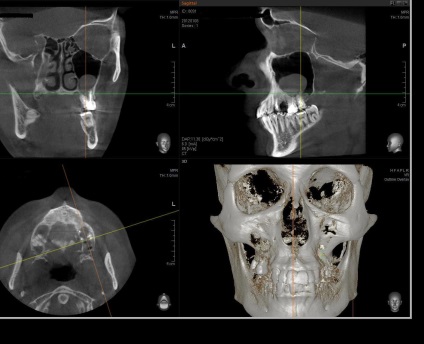

A fő kutatás módszere a feltétele az arcüreg is egy X-ray, és a rendes vetülete (kétdimenziós) képeket, itt az ideje elfelejteni. Megbízhatósága és pontossága csak 25-30%.

Diagnózis a odontogenikus ciszták szükségképpen leolvasó, lehet, hogy egy multislice vagy, megint csak a kúp nyaláb tomográfia. A beolvasási terület kapjon a középső és felső harmadában az arc.

Meg kell jegyezni, hogy még a legkifinomultabb módszereit sugárzás kutatás nem zárja ki, hogy szükség van az ellenőrzés. Ellenőrzés sinus feltárja a legapróbb szöveti változásokat és funkcionális károsodás, hogy nem áll rendelkezésre más módszerekkel. Különösen csak felmérés pontosan meg tudja határozni, hogy a tartalom telt ciszta, a zóna a felerősítését, és így tovább.